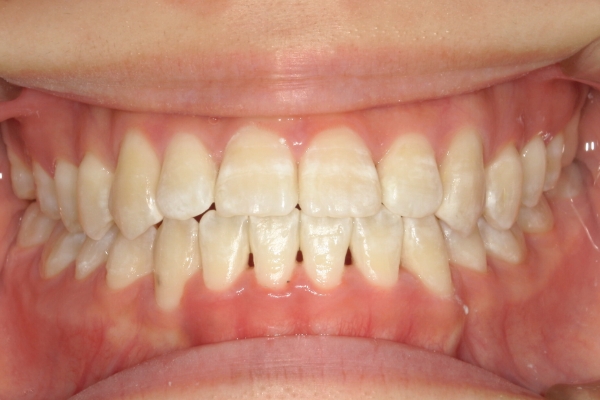

AFTER

治療後

骨格的に下あごが前下方に長いことが原因で、受け口、開咬(前歯が当たらない)の症状がでていました。また下あごが右にずれており、その影響で上下の歯列正中(真ん中)の大きなずれも生じていました。顎変形症手術も選択肢の一つでしたが、患者さまの希望もあり、下顎左側小臼歯の抜歯をして通常の歯列矯正で治療をしました。

前歯、奥歯の噛み合わせが大きく改善され、上下の歯真ん中が一致しました。食べ物が噛みやすくなったこともですが、歯列の見た目が整った点にも患者さまは満足されていました。